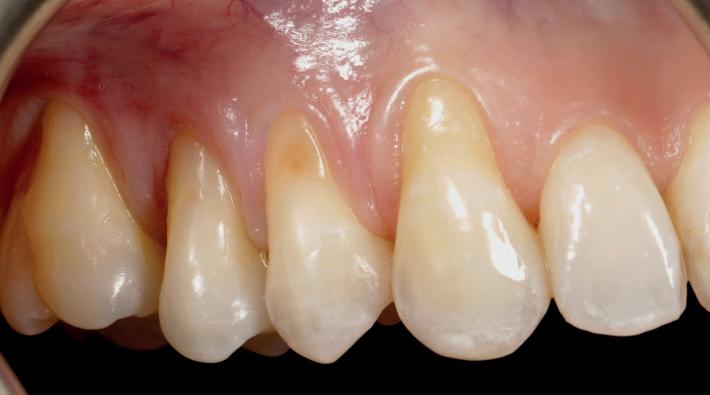

Exposed roots

Gingival recession